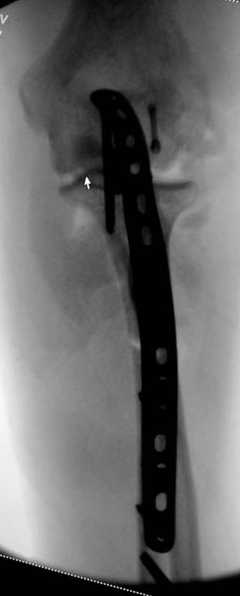

В начале недели видел снимок (больного -нет). Конечно, венечный отросток сломан. Сложности возникают из-за небольших размеров верхушки локтевого отростка и первичного дефекта. Не везде имеются специальные пластины. Мы обходимся обычной трубчатой пластиной + проволочная петля. Снимки, похожие, выложу позднее (необходимо отредактировать).

Для фиксации перелома локтевого отростка на сегодня множество преконтурных с блокирующими возможностями пластин.

Стабильную фиксацию, особенно при оскольчатых

переломах, можно добиться, применяя технику Bridge Plate, и за счет тех пластин, где имеется возможность проведения множественных шурупов (2.7 мм) проксимально.

Здесь выставлены несколько случаев и варианты фиксации локтевого отростка, некоторые в комбинации с другими переломами.

1 вариант применен ACUMED локинг пластина

2 вариант

перелом локтевого отростка с переломом головки лучевой кости (использованы 2 мм шурупы)

3 вариант

перелом с capitelum humerus и проксимальной трети улна